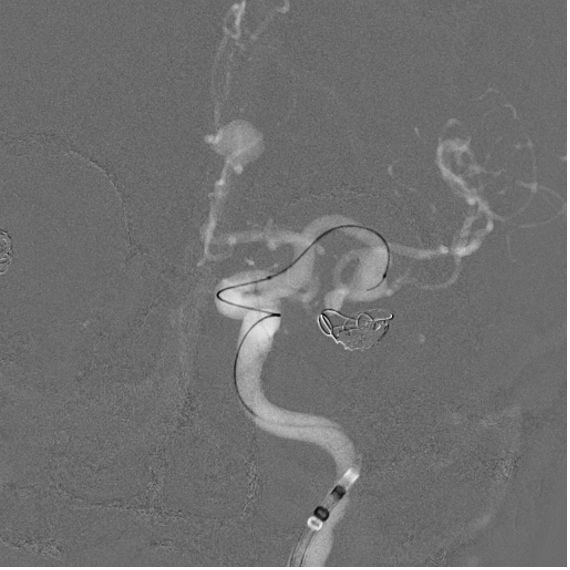

• Under general anesthesia, a puncture was performed on the right femoral artery, and a CEREBASE 8F introducer catheter was inserted.

• The left internal carotid artery (ICA) was accessed and a pathway was built using TJWY’s FREPASS microcatheter.

• A 5x20mm NUVA flow diverter, designed by TJWY, was deployed to treat the aneurysm in the posterior communicating artery with precision, achieving immediate blood flow stagnation.

• The neck of another aneurysm in the pericallosal artery was protected with a 10mm PCONUS intrasaccular device, and successfully embolized with 3 coils.